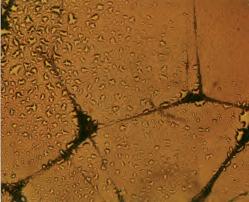

"Nauka jako sztuka" jest ideą autorstwa Augusta Kowalczyka, aktora, reżysera i byłego więźnia obozu koncentracyjnego

Auschwitz

Zdjęcie "Fioletowe wybrzeże" przedstawia mikroskopowy obraz wycinka nerki, z zabarwionym na fioletowo kolagenem. Zdjęcie to zostało wykonane w Dr Rath Research Institute

Pełna galeria zdjęć jest dostępna pod adresem:

www.dr-rath-humanities-foundation.org/exhibition/index.html

„Fioletowe wybrzeże“